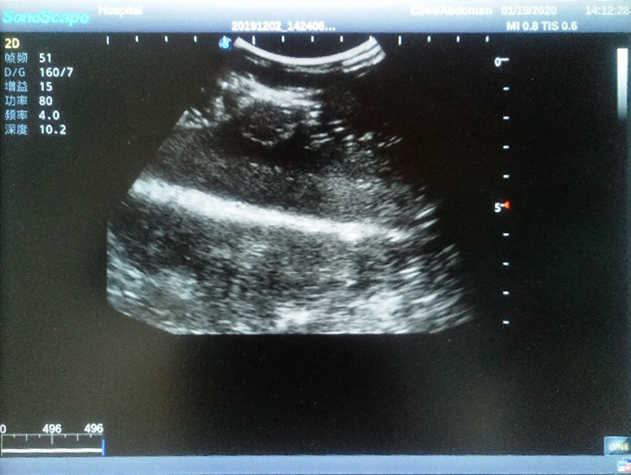

2) Each model contains 8 space-occupying lesions of varying sizes, different in touch, elasticity and ultrasonogram

4) Biomimetic material allowing users to see clear and real normal tissues and space-occupying lesions that are hyperechoic, hypoechoic and isoechoic as they would see in the clinical environment